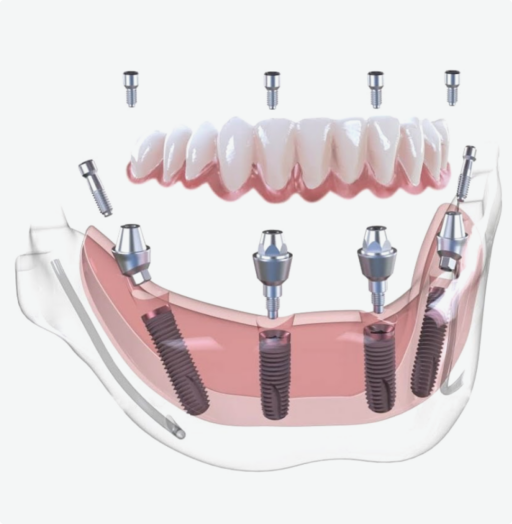

Что такое имплантация

All-on-4

Что такое имплантация

All-on-4

Протез устанавливается не на опорные зубы (которых при полной адентии и нет), а на предварительно вживленные 4 импланта. Импланты устанавливаются в кость челюсти в заранее определенные участки, и затем на имплантах фиксируется зубной протез

Имплант имеет сложное строение, включающее три базовых элемента:

Установка имплантов

4 импланта с одномоментным удалением больных зубов

Мультиюнит абатменты

Оригинальные абатменты для винтовой фиксации протеза